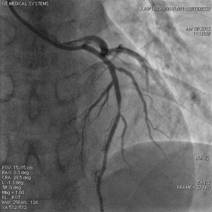

![]() 冠動脈狭窄

ステント挿入後

急性の心筋梗塞・くも膜下出血・脳梗塞・動脈出血などに対応するアンギオ装置です。

24時間いつでも対応しております。